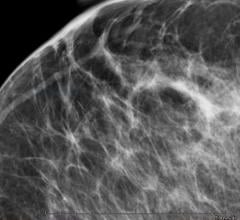

Prestige Medical Imaging (PMI) will partner with VuCOMP Inc., a developer of advanced computer vision systems for the detection of breast cancer. VuCOMP has developed and commercialized two breast-imaging products, M-Vu CAD and M-Vu Breast Density. M-Vu CAD analyzes mammograms to mark areas consistent with breast cancer using sophisticated mathematical algorithms.

April 15, 2014 — VuComp Inc. announced it has released an updated version of its M-Vu Breast Density technology. The new M-Vu Breast Density 2.0 adds a critical dimension to the analysis of dense breast tissue. The VuComp density category, analogous to the BI-RADS breast density composition category, is now correlated to not only the amount, but also the distribution – the actual dispersion – of fibroglandular tissue.